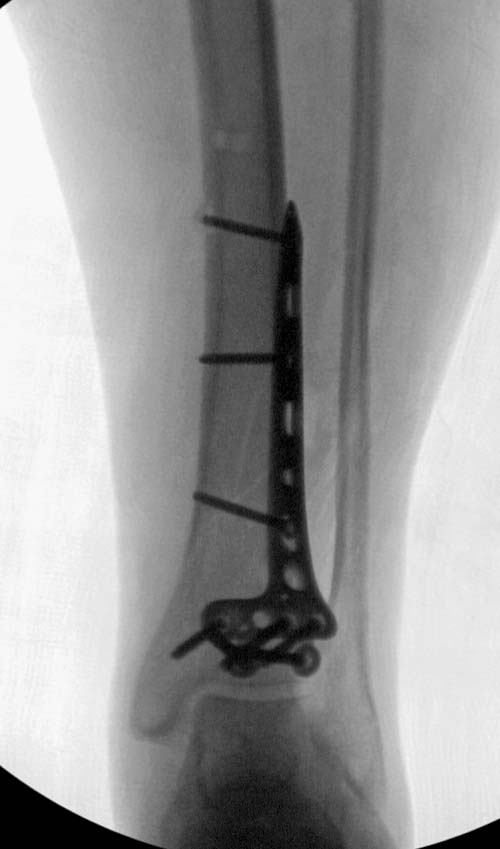

Второй случай в результате скоростной травмы, кроме пилона, вовлечение

других органов! Отек при поступлении и открытый перелом на другой

стороне. В таких случаях нет смысла спешить, и временный наружный

фиксатор на несколько дней. После спадения отека фиксация

передне-наружной пластиной.  Реабилитация - ранние движения, без

нагрузки.